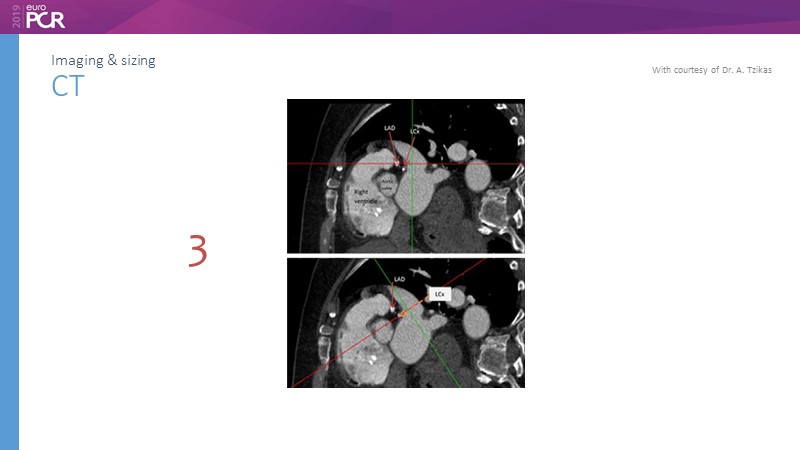

Pre-procedure planning

Previous Next